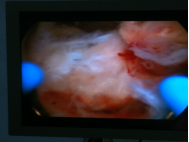

诊疗过程:入院后完善相关辅助检查,予以在腰麻下行宫腔镜电切术:患者取膀胱截石位于手术台上,腰麻成功后,碘伏常规消毒会阴部手术野皮肤及阴道,妇科检查:外阴已产式,阴道畅,分泌物少,无异味,宫颈轻度糜烂,无举痛。子宫常大,无压痛。双附件未及明显异常。探宫腔225px,用20%甘露醇作膨宫液行宫腔镜检查术,宫腔形态规则,宫腔内右后壁近输卵管开口处见4.0*2.5*50px胎盘机化绒毛样肿物突起,内膜少,两输卵管开口清晰可见,宫颈管形态正常,用环形电极行电切术,术中见深达肌层。符合“胎盘植入”。充分止血后。检查宫腔形态正常。术毕。切除物送病理检查:坏死组织中有少许子宫内膜及钙化、机化组织。